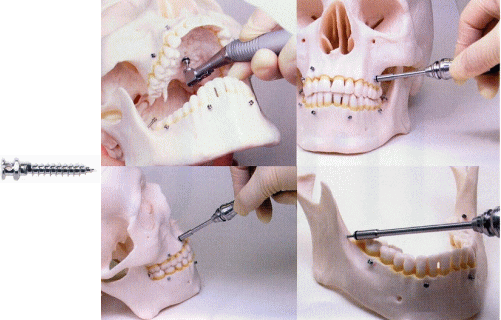

ミニインプラントとは

- 生体適合性に優れた純チタン製です

- 6~9mmの長さのスクリューがあります

- 径は1.2 mmと1.6 mmです

- 外科的侵襲は最小限に抑えています

当医院では、オーザスというミニインプラントを使用しています。

オーザスとは、Osseo-dyne Skeltal Anchorage Systemの略で、OSASと綴ります。外科的矯正治療用骨接合用品のひとつです。最近では、TADともいわれ、Temporally

Anchorage Deviceの略です。

OSAS/TAD(テンポラリアンカレッジデバイス、ミニスクリュー)は、顎骨や歯槽骨の骨折または顎顔面変形や不正咬合時の外科的矯正治療に使用するものとして薬事の承認を受けております。

OSASはチタン合金の骨接合用品であり、顎骨や歯槽基底部、あるいは歯槽骨などに埋入し使用します。

スクリュー長は5, 6, 7, 8, 9 mmがあります。直径は1.6mmで、パイロットドリルなしのセルフタッピングで植立します。

ドイツ製で破折の危険性が少ない頑強な設計です。脱落しにくいシリンダータイプの形状です。

骨化しないため、治療終了後容易に撤去できます。